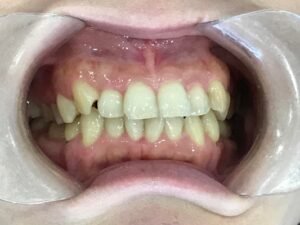

▼治療前(Before)

上顎・下顎ともに歯が重なり合っており、特に上の前歯には強い叢生が確認できます。

歯ブラシが届きにくく、清掃性も低下していました。